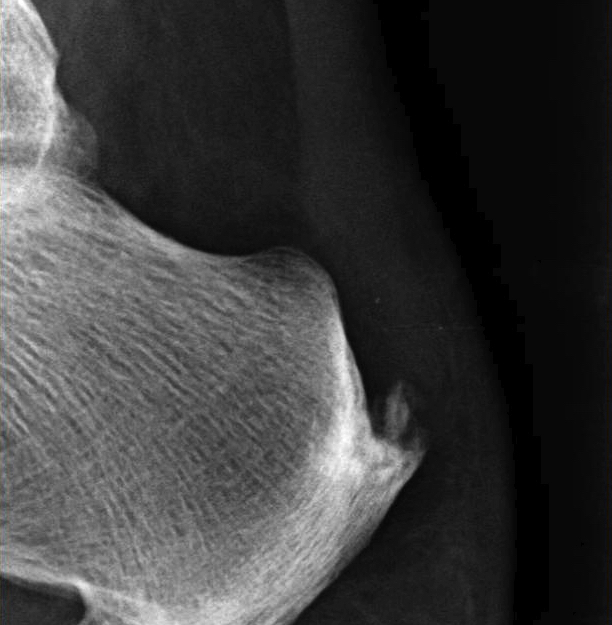

X-ray

Insertional achilles tendon spurs

- also present in asymptomatic patients

Calcification of bone-tendon interface with spur

Haglund's Deformity

- bony protuberance of posterosuperior calcaneus

Pavlov's parallel pitch lines

- lateral weight bearing x-ray

- draw parallel pitch lines

- defines Haglund's deformity to be removed (above second line)

Fowler's angle - Normal < 70° / Abnormal > 80°